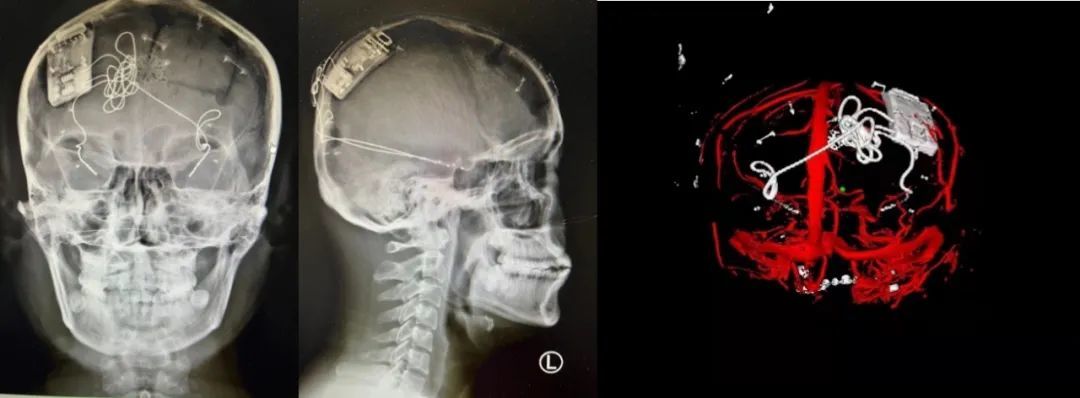

本次手術(shù)過程順利,術(shù)中刺激器各項指標(biāo)均工作正常,術(shù)后重建顯示電極位置精準(zhǔn),腦電信號清晰?;颊邽槟行裕朐汉笤\斷為雙側(cè)顳葉癲癇,此類癲癇為開顱手術(shù)的相對禁忌癥,在藥物無法控制的情況下,傳統(tǒng)治療效果欠佳 。

團(tuán)隊根據(jù)術(shù)前計劃,在手術(shù)機(jī)器人輔助下完成雙海馬長軸電極及 IPG 植入,術(shù)后重建顯示電極位置精準(zhǔn),腦電信號清晰。術(shù)后第二天,患者即下床活動,身體狀況恢復(fù)良好。